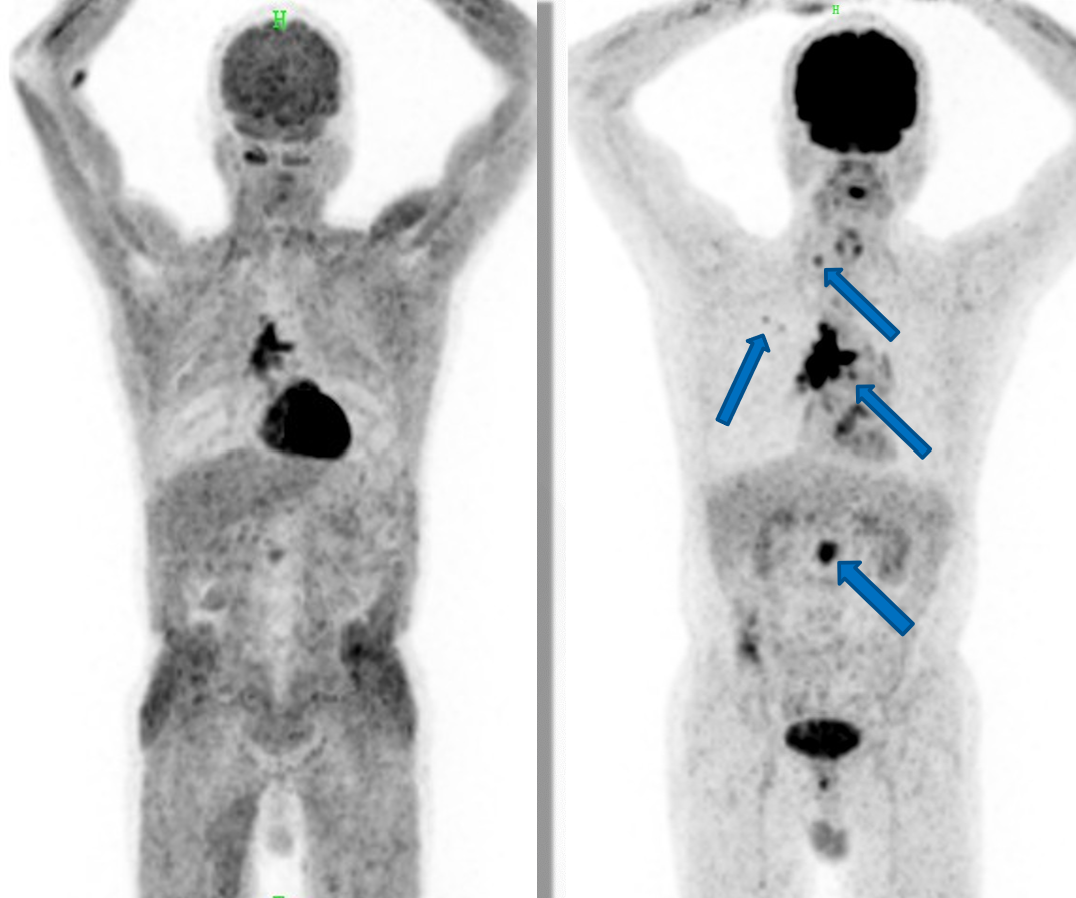

左图为检查前未禁食的图像,右图第二天空腹重做的图像,箭号所示为病灶。